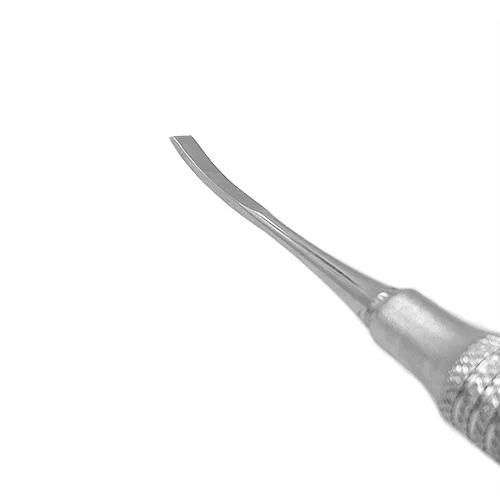

Scalpello Kramer Nevis TG

Lo Scalpello Kramer–Nevins TG è uno strumento chirurgico odontoiatrico professionale progettato per il modellamento, la rifinitura e la regolarizzazione dei margini ossei durante interventi di chirurgia orale e implantologia. Grazie alla sua parte attiva doppia con geometrie differenziate, consente un controllo preciso nelle diverse fasi di lavorazione dell’osso, adattandosi efficacemente all’anatomia del sito chirurgico.

La prima estremità presenta una lama da 3 mm leggermente ricurva, con punta terminale dritta, studiata per seguire il profilo osseo e facilitare interventi di rifinitura in aree concave o difficilmente accessibili. La seconda estremità è caratterizzata da una lama più ampia da 3,5 mm, dritta, con terminale leggermente pendente, ideale per il livellamento controllato delle superfici ossee e per il rimodellamento dei margini corticali.

Questo tipo di configurazione, tipica degli scalpelli Kramer–Nevins utilizzati in chirurgia implantare e rigenerativa, permette di operare con precisione sia in fase di preparazione del sito implantare sia durante procedure di chirurgia ossea correttiva.

Parte attiva doppia:

estremità da 3 mm, leggermente ricurva con punta terminale dritta,

estremità da 3,5 mm, dritta con terminale leggermente pendente.

Manico ergonomico: diametro 9 mm, con striature antiscivolo per una presa stabile e sicura anche in presenza di umidità.

Materiale: acciaio inossidabile chirurgico di alta qualità, resistente alla corrosione, biocompatibile e completamente autoclavabile.

Lo Scalpello Kramer–Nevins TG rappresenta uno strumento essenziale per il professionista che esegue interventi di chirurgia ossea e implantologia. La parte attiva doppia da 3 mm e 3,5 mm, con differenti conformazioni, il manico ergonomico da 9 mm e la costruzione in acciaio inossidabile chirurgico garantiscono precisione, controllo e affidabilità in ogni fase dell’intervento chirurgico.